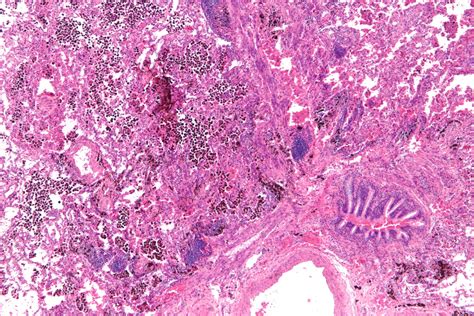

Diffuse Alveolar Hemorrhage occurs when there is bleeding into the alveoli, the tiny air sacs in the lungs responsible for gas exchange. This bleeding can be caused by a variety of factors, including autoimmune disorders, infections, and certain medications. The condition can lead to respiratory failure if not treated promptly.

• Bronchoscopy: This procedure involves inserting a thin tube with a camera into the lungs to directly visualize the bleeding.